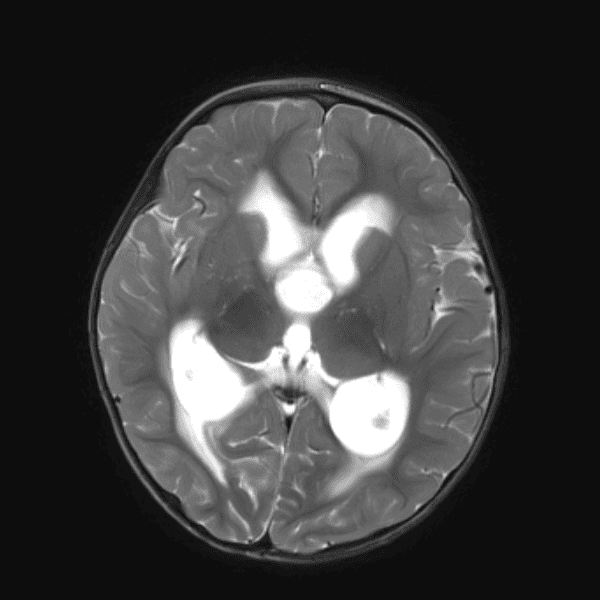

Classic Cases